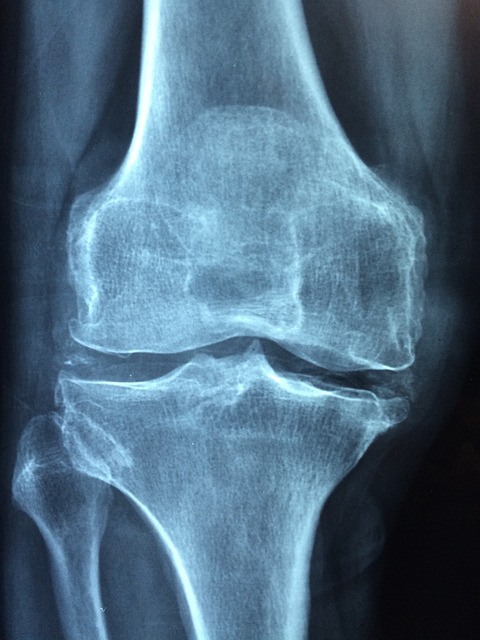

✅ 골다공증이란?

골다공증은 단순히 뼈의 문제만이 아니라 골수와 피부에도 영향을 미치는 질환입니다. 주된 원인은 칼슘과 비타민 D 부족으로, 이들 영양소는 뼈 건강에 필수적입니다. 식생활, 운동, 생활 습관이 골다공증 예방에 중요한 역할을 합니다. 현재 골다공증 치료는 충분하지 않으며, 올바른 영양 섭취가 필요합니다.

• 나이가 들면서 칼슘이 고갈되면 갑상선이 혈액으로 칼슘을 끌어내고, 결과적으로 뼈에 구멍이 생깁니다.

• 골다공증은 뼈뿐만 아니라 신체 전반에 영향을 미치는 질환입니다.